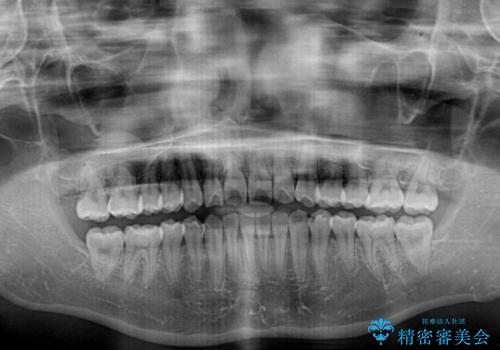

- 上下のデコボコと前歯のクロスバイトを改善したいとのことで来院された患者様です。

極力短期間で治療したいとのことで、ワイヤー装置による矯正治療を行うこととしました。

お住まいが遠方であったため、マウスピースによる矯正治療も提案しましたが、ご自身でのマウスピースの管理の面倒くささと、なるべく早く治療を終えたいとのことで、ワイヤー矯正を選択されました。